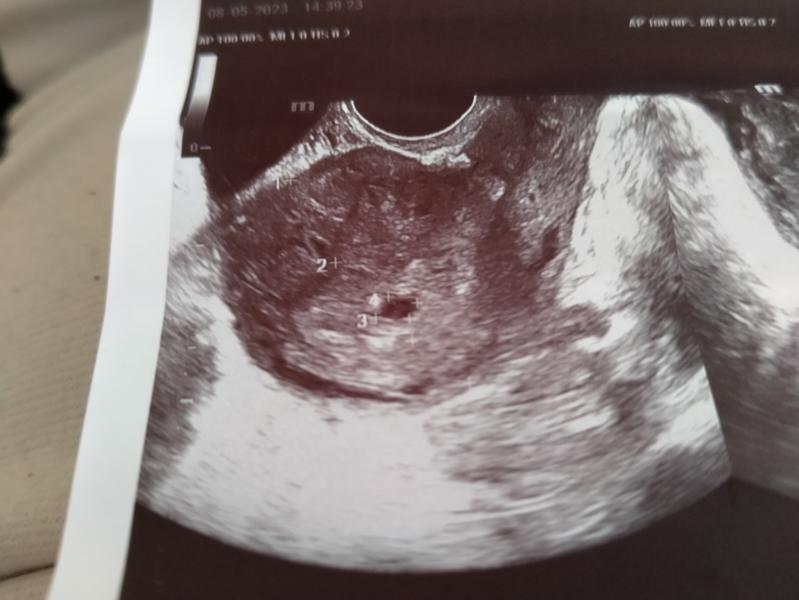

Девочки, срок по узи 6,1 нед(по узи плодное яйцо на 5 недель) Матка по УЗИ увеличена на 8 нед.

Узистка предположила , что два ЖЕЛТОЧНЫХ МЕШКА. А вы что-нибудь видите?